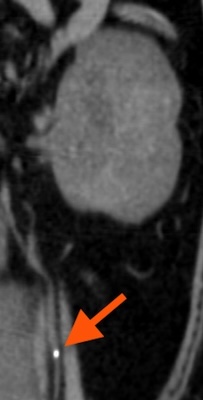

全身麻酔下でのCT検査では尿管結石あり(右 1.0mm、左2.0mm程度)。

右尿管からは1.0mm、左尿管からは2.5mm程度の結石をそれぞれ摘出しました。